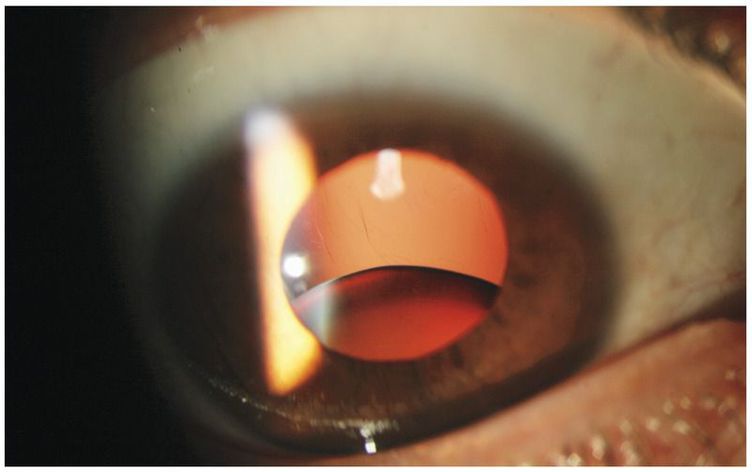

A 41-year-old man presented with progressive loss of vision in both eyes that was worse in the right eye than in the left. There was no history of trauma. His uncorrected visual acuity was 6/200 in the right eye and 20/100 in the left eye. Slit-lamp examination revealed ectopia lentis in both eyes, including near-complete inferior dislocation of the lens in the right eye (shown above) in addition to visible stretched zonules (the suspensory strands of the lens) and inferotemporal subluxation of the lens in the left eye. The patient’s mother has Marfan’s syndrome, and the patient has the elongated digits and pectus excavatum that are characteristic of the disease. He underwent pars plana vitrectomy and implantation of a scleral-sutured intraocular lens in the right eye. At final follow-up, the best corrected visual acuity in the right eye was 20/20, with correction of myopia. Marfan’s syndrome is associated with ectopia lentis in both eyes, a characteristic that may be subclinical. Indications for surgery include correction of an otherwise unmanageable difference in refractive power between the two eyes (anisometropia), excessive induced astigmatism, and complications of lens subluxation, including glaucoma, uveitis, and retinal detachment.